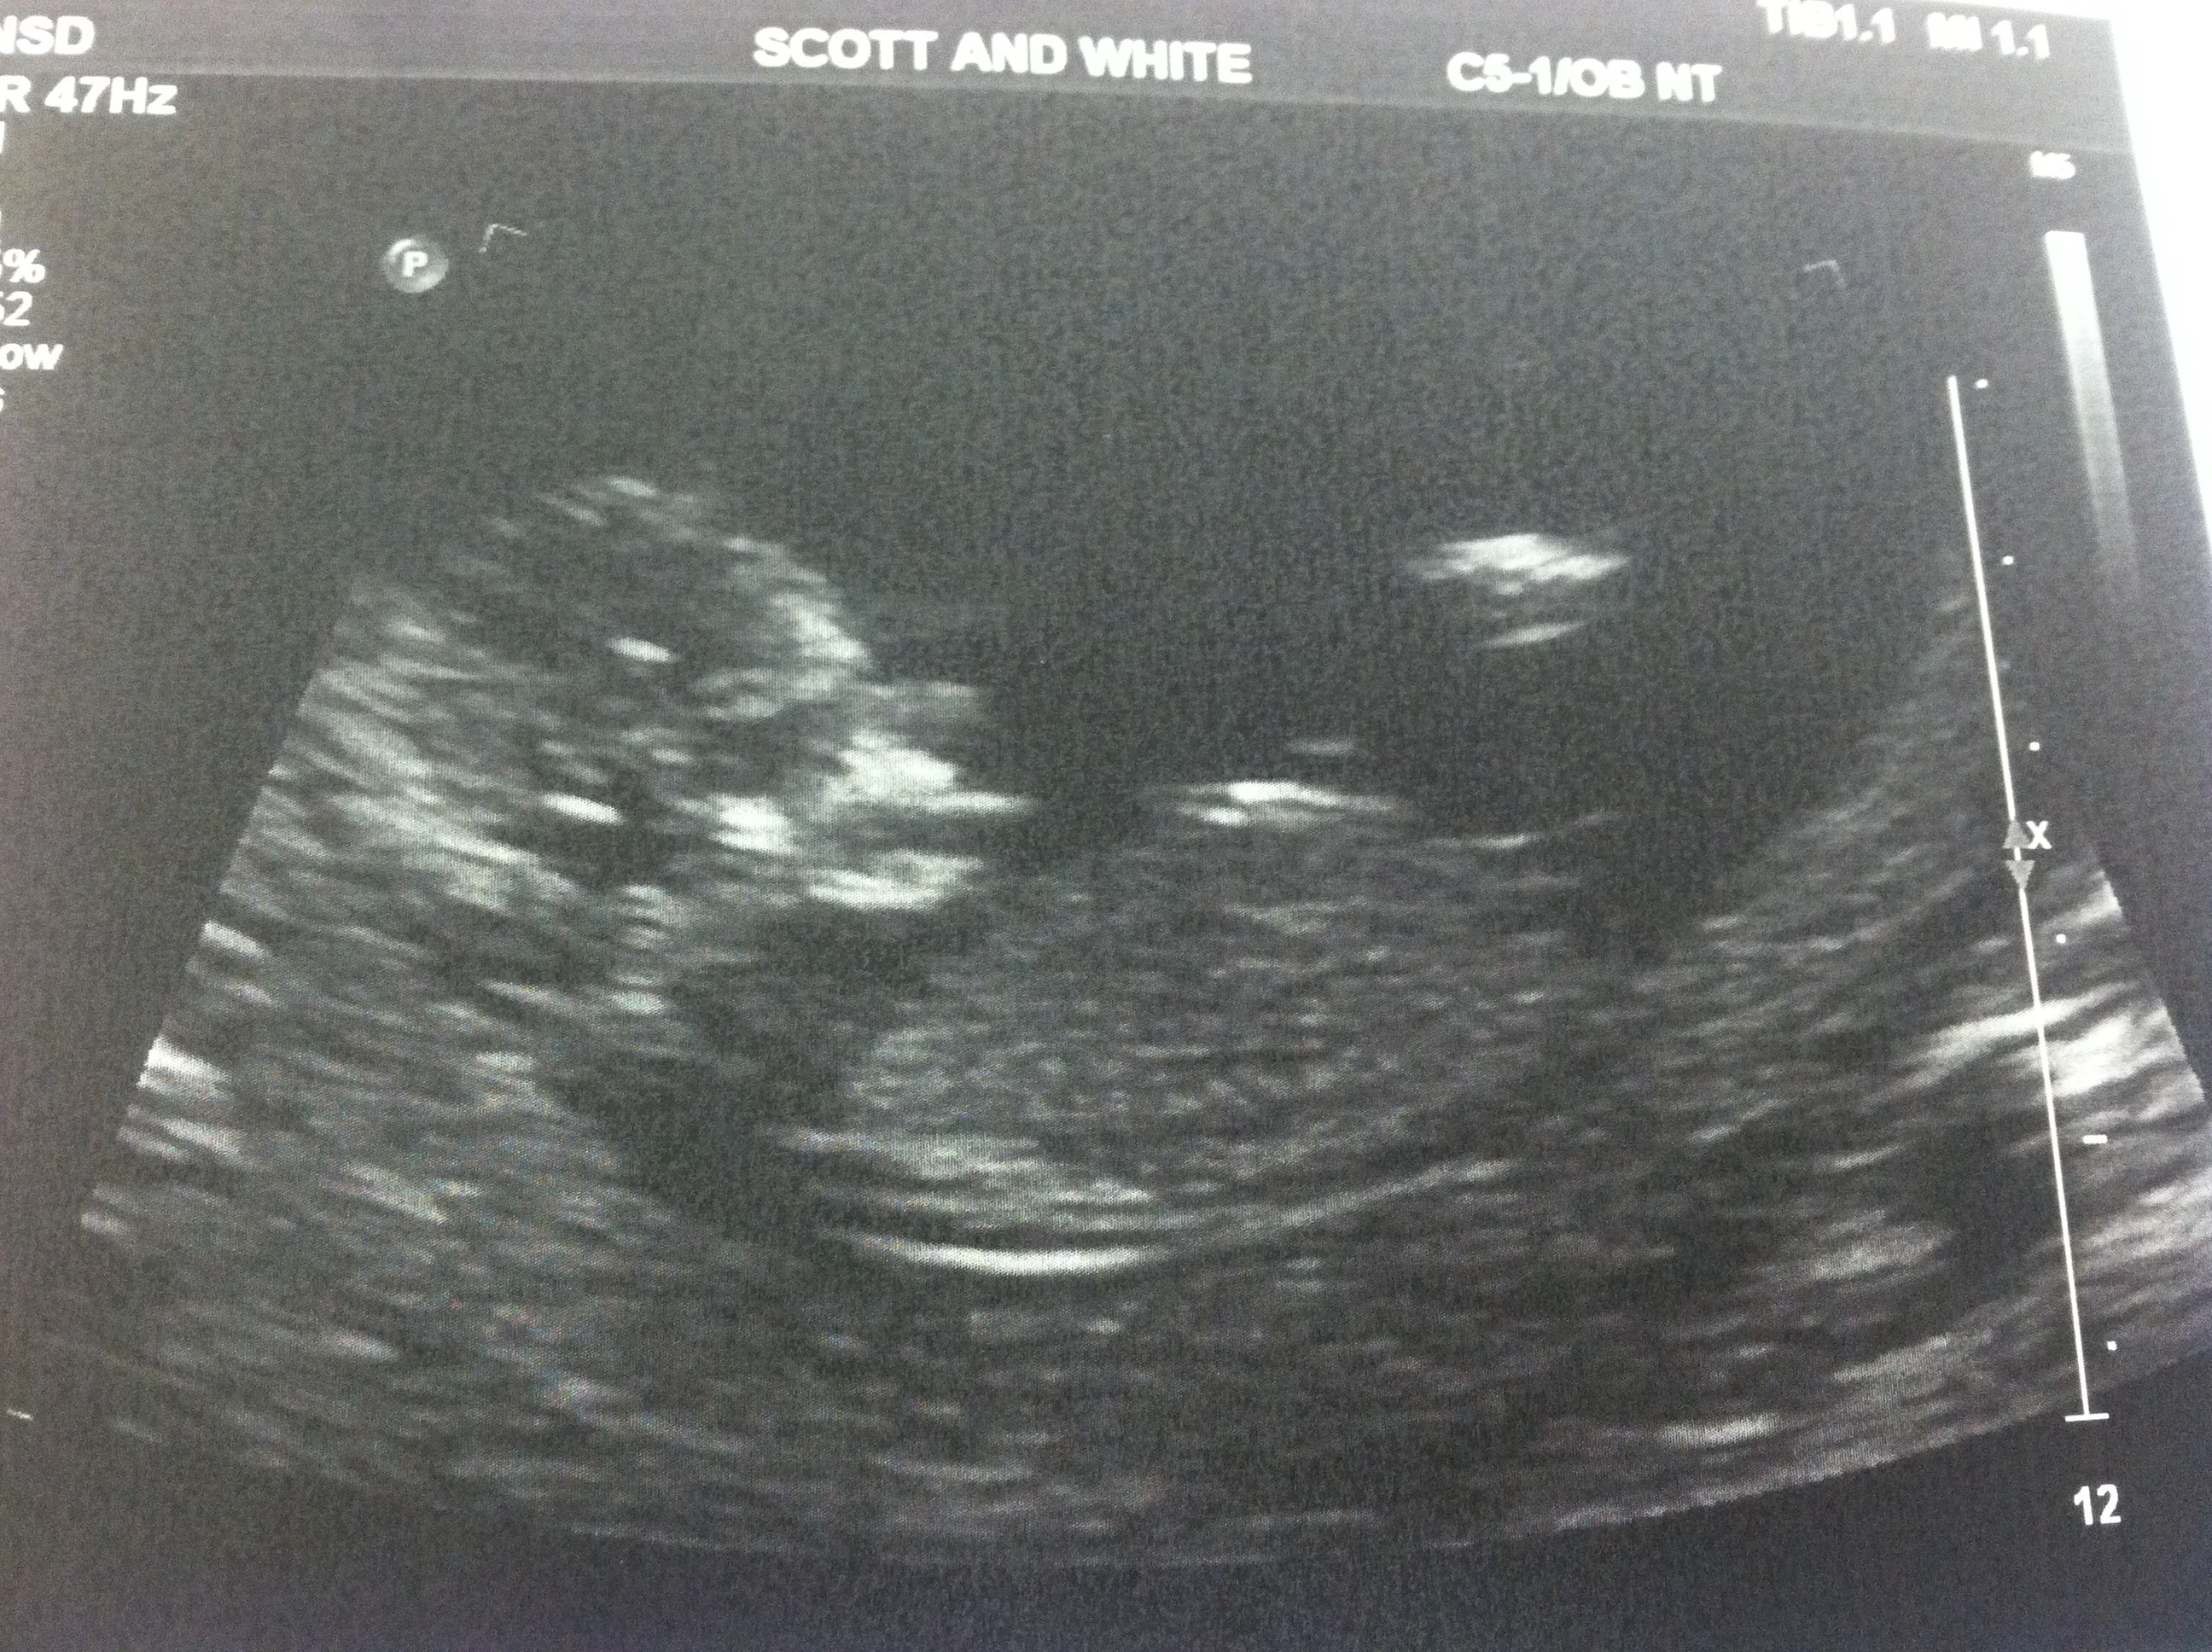

13w2d pics- ITS A GIRL!!! THANKS FOR GUESSING :)